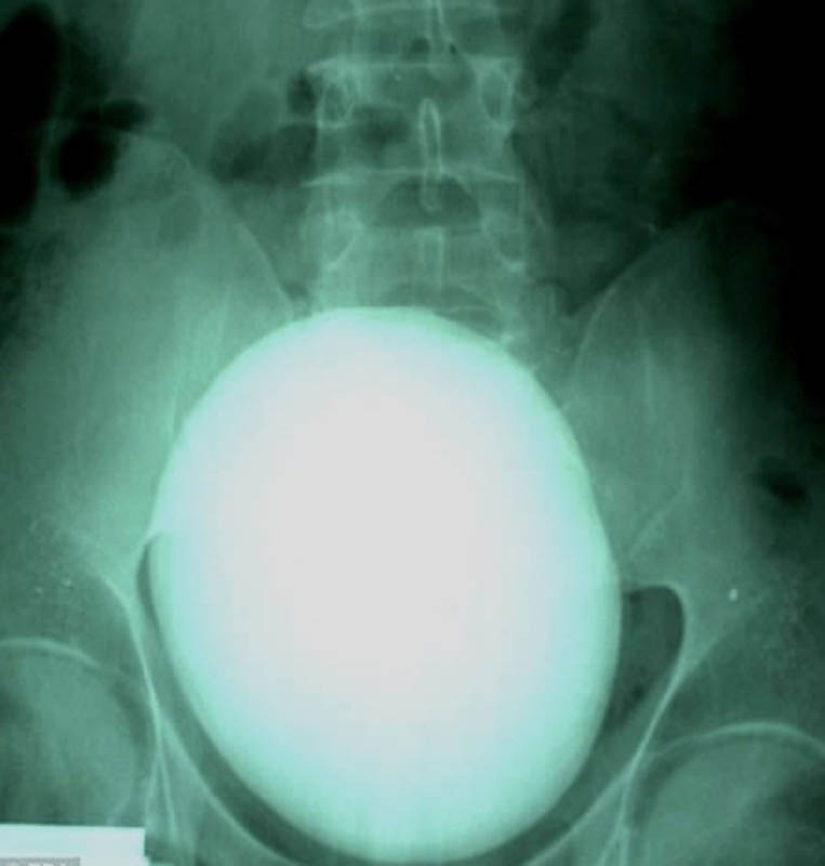

17. Such a 15-centimeter kidney stone weighing 1.1 kilograms was removed by a patient from Hungary.